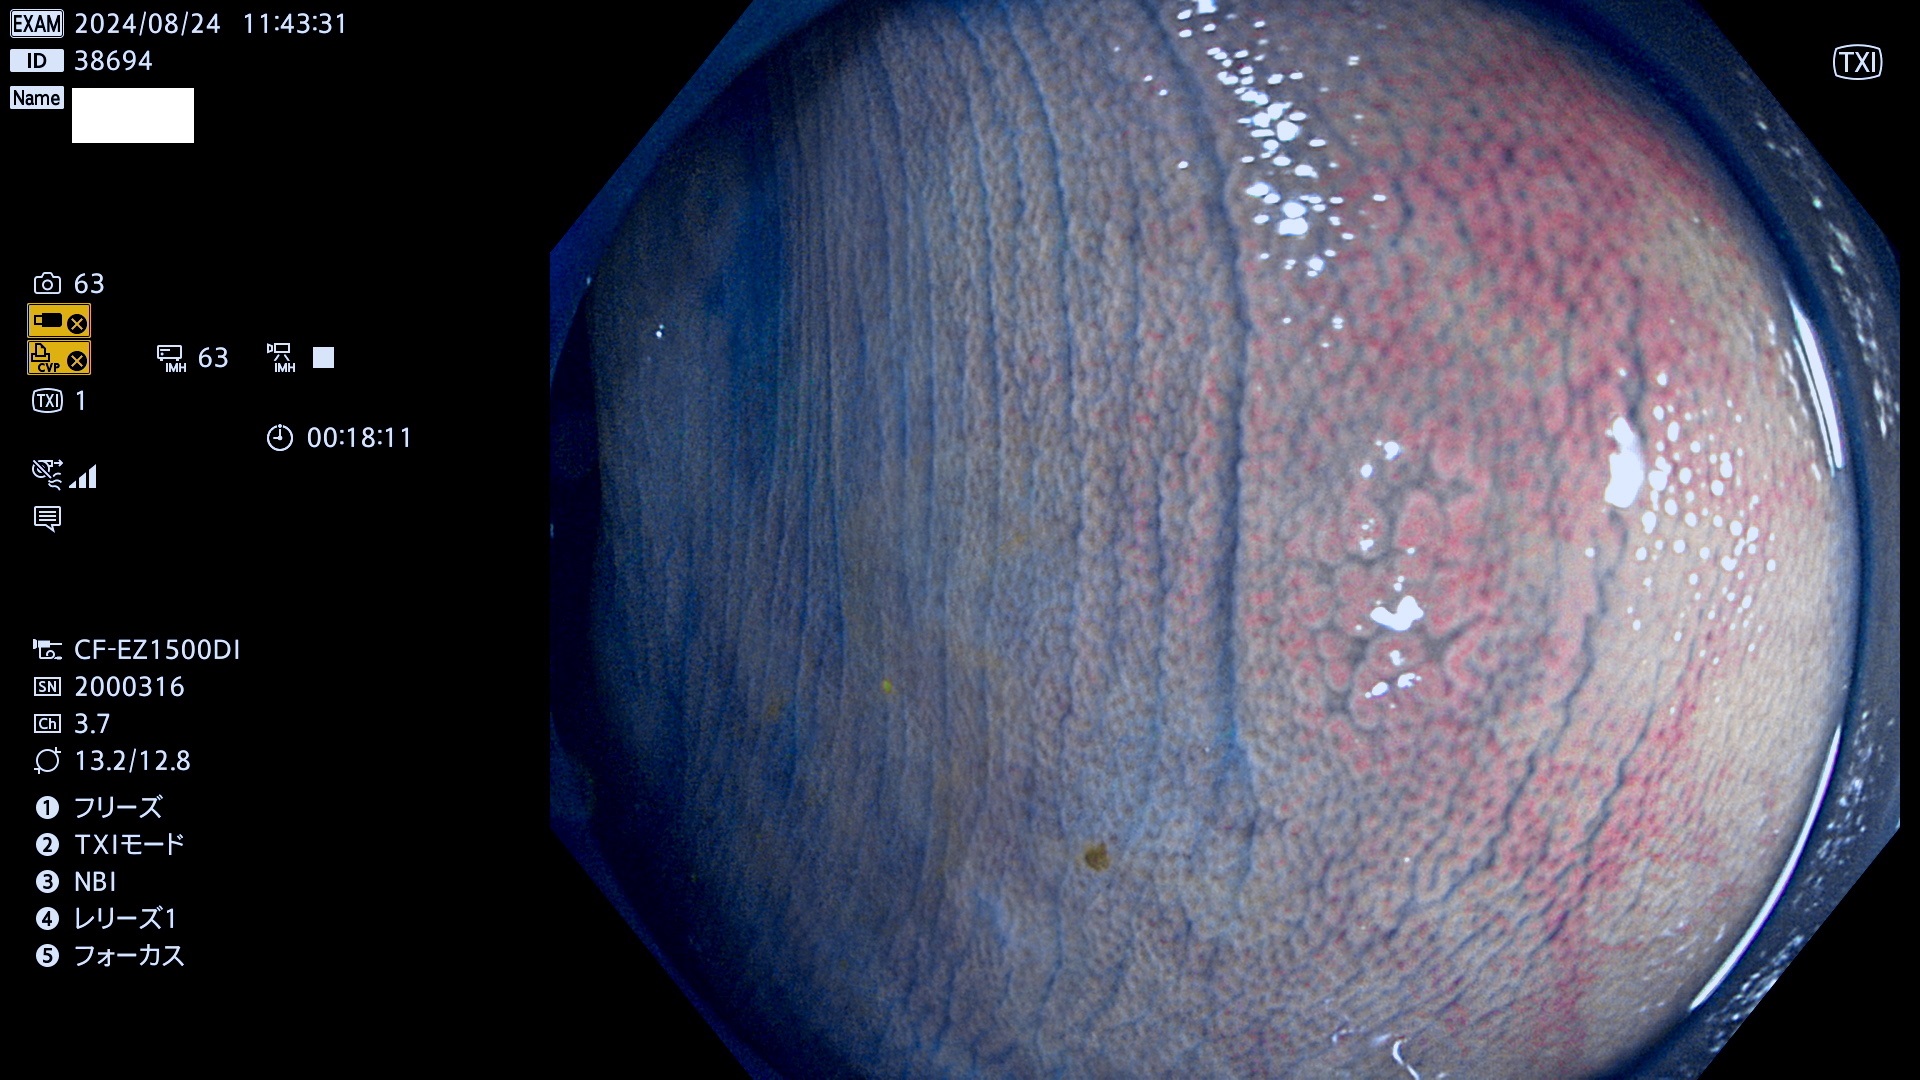

完全に平坦な物をUb、陥凹している物をUcと呼びます。最も発見が難しく危険な病変です。

専門的)Uc=De Novo癌? 内視鏡の解像度が低かった時代、このような説もありました。しかし今日の高精度内視鏡では良性の微小なUc型腺腫が日常的に見つかります。私見ですが「Ucこそが多段階発癌(Adenoma-Carcinoma Sequence)のMain Route」と考えます。

毎週の検査(木・金・土・日)に発見されたUb、Uc型・腺腫を、その週の日曜の夜にUPし1週間、提示します。

抽出の対象期間 2024年8月22日〜8月25の4日間(33件の検査)7件 (7/33=21%)